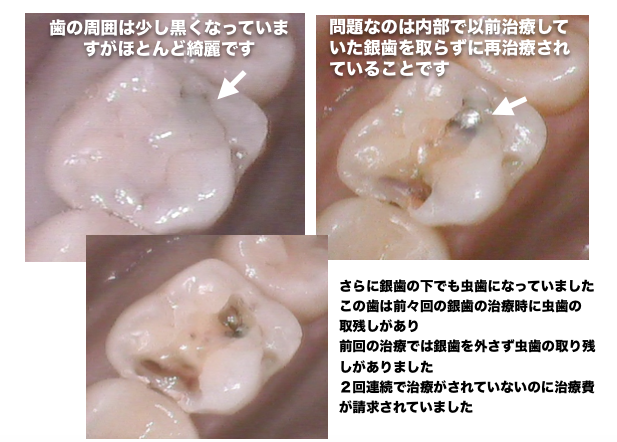

1本の歯に2回連続で虫歯の取り残しが見つかった症例

上記の写真はここまで虫歯になっていても痛みが全くない症例でした

以前治療した銀歯の内部から虫歯の取り残しが見つかった症例

銀歯の内部で虫歯の取り残しがあった症例

治療していると、過去に治療したレジン治療や銀歯治療の内部で虫歯の取り残しが多く見られます

治療を受ける際は、必ず内部で虫歯の取り残しがないかどうか自分の目で確認できる歯科医院を選択することをオススメしています

治療を受ける際は、幹部の写真を撮影している歯科医院をお勧めしています

きちんと虫歯を治療しているかどうかはご自身の目で判断することが重要です

虫歯はほとんど痛みもなく神経まで到達します